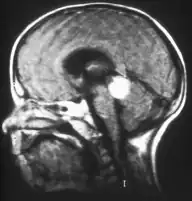

Inherited forms of retinoblastomas are more likely to be bilateral. In addition, inherited uni- or bilateral retinoblastomas may be associated with pineoblastoma and other malignant midline supratentorial primitive neuroectodermal tumors (PNETs) with a dismal outcome; retinoblastoma concurrent with a PNET is known as trilateral retinoblastoma.[17] A 2014 meta-analysis showed that 5-year survival of trilateral retinoblastoma increased from 6% before 1995 to 57% by 2014, attributed to early detection and improved chemotherapy.[18]

In about two-thirds of cases,[29] only one eye is affected (unilateral retinoblastoma); in the other third, tumors develop in both eyes (bilateral retinoblastoma). The number and size of tumors on each eye may vary. In certain cases, the pineal gland or the suprasellar or parasellar region (or in very rare cases other midline intracranial locations) is also affected (trilateral retinoblastoma). The position, size, and quantity of tumors are considered when choosing the type of treatment for the disease.

Aspect of trilateral retinoblastoma on MRI -